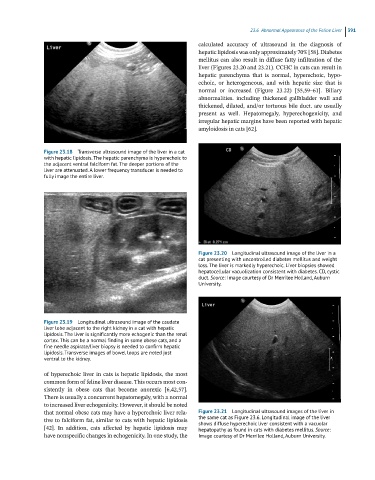

Figure 23.20 Longitudinal ultrasound image of the liver in a

cat presenting with uncontrolled diabetes mellitus and weight

loss. The liver is markedly hyperechoic. Liver biopsies showed

hepatocellular vacuolization consistent with diabetes. CD, cystic

duct. Source: Image courtesy of Dr Merrilee Holland, Auburn

University.

that normal obese cats may have a hyperechoic liver rela- Figure 23.21 Longitudinal ultrasound images of the liver in

tive to falciform fat, similar to cats with hepatic lipidosis the same cat as Figure 23.6. Longitudinal image of the liver

shows diffuse hyperechoic liver consistent with a vacuolar

[42]. In addition, cats affected by hepatic lipidosis may hepatopathy as found in cats with diabetes mellitus. Source:

have nonspecific changes in echogenicity. In one study, the Image courtesy of Dr Merrilee Holland, Auburn University.